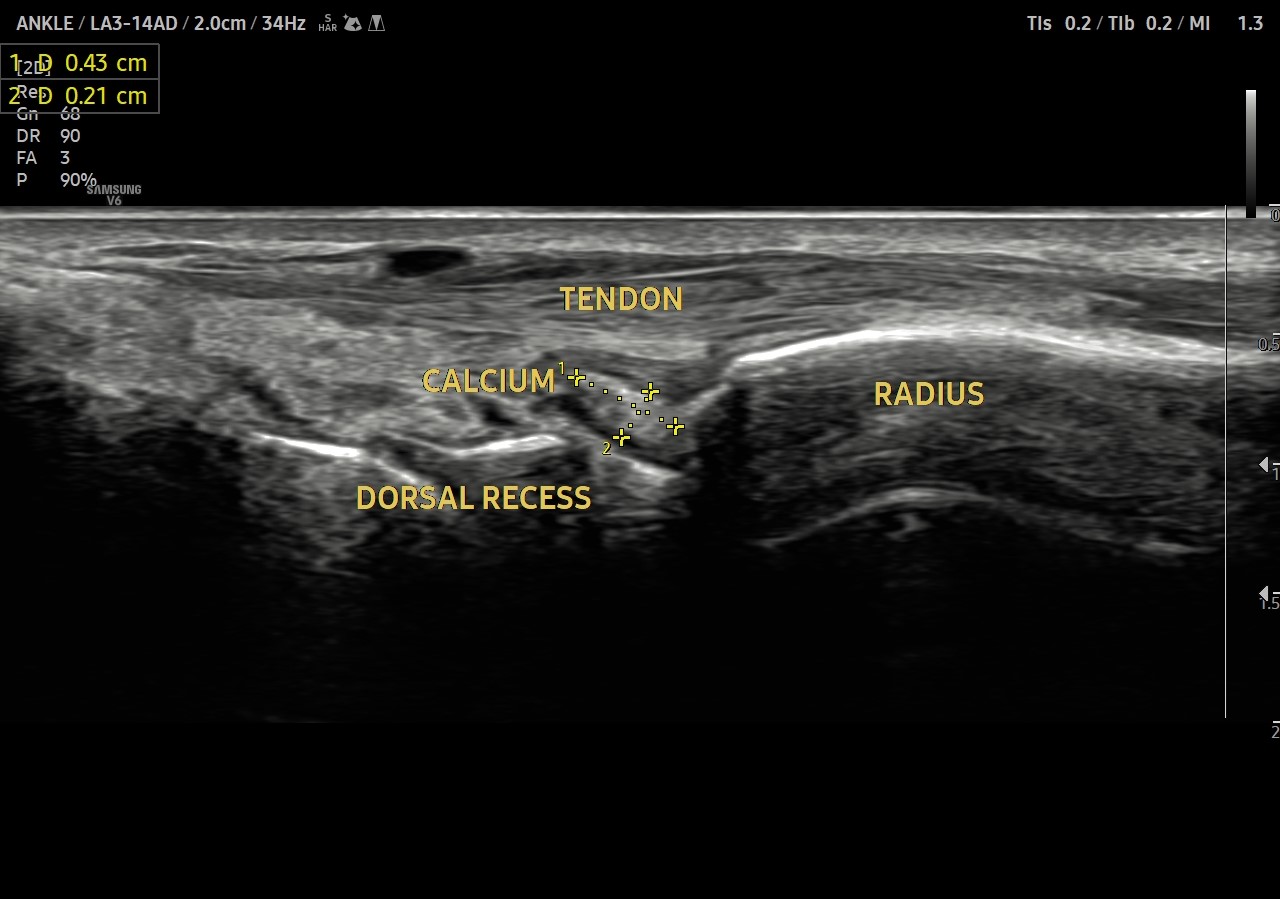

Soft calcium

Case of Calcific periarteritis - soft calcium deposition in the dorsal recess of wrist joint causing inflammation and pain